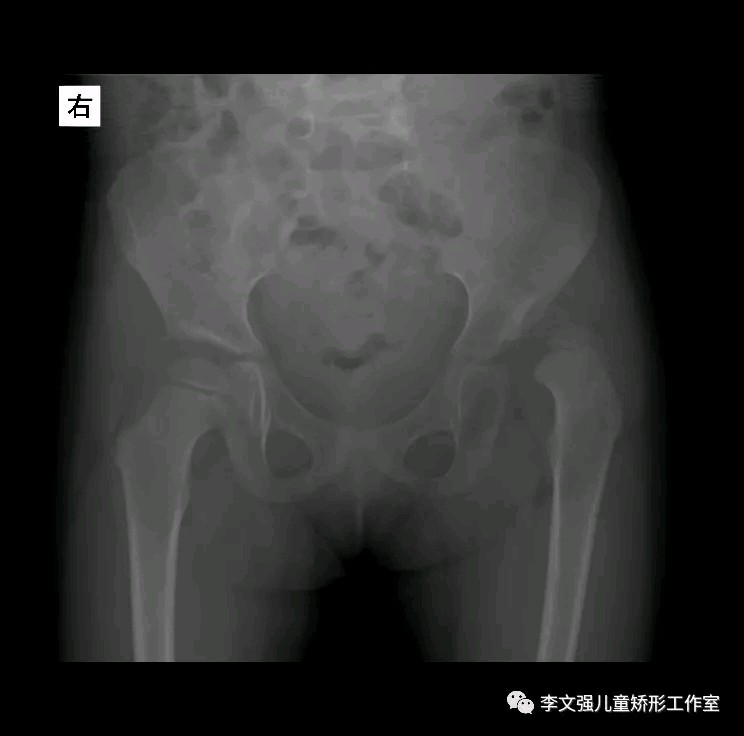

小儿发育性髋关节脱位是一种常见的髋关节疾病,女孩多于男孩。病变累及髋臼、肌骨头、关节囊、韧带和附近的肌肉,导致关节松弛,半脱位或脱位。

该病的主要表现:(1).多见于女性婴幼儿,可有家族史。(2).大腿的皮纹不对称;双下肢不一样长等。两则臀皱纹和大腿皮纹不对称,腹股沟纹深而位高,患肢较短。双侧脱位者,会阴部增宽,有些细心之母亲可发现上述变化外,也会发现病儿大腿不易分开,往往在换尿布时发现髋部有弹跳现象。(3).站立步行迟,跛行。单侧脱位为短腿跛行,双侧脱位呈左右摇摆之鸭步。(4).外展受限,患侧臀皱纹增多。(5).双侧脱位时,臀部后耸,腰前凸。如果发现上述症状我们要及时到医院做进一步的检查,以免延误治疗。患儿出生后可以到医院做B超筛查。

双侧DDH,行双侧Salter截骨矫形+股骨近端短缩去旋转截骨手术